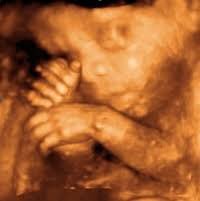

@TheRationaliste you said: À women is a person, an embryo isn't one, so this argument is fallacious. well, this is how old i was when i was born in an abortion clinic as a female. 29 1/2 weeks. the pain system develops at 28. i felt everything. i have cerebral palsy as a result.pic.twitter.com/8cUSzY7fqD